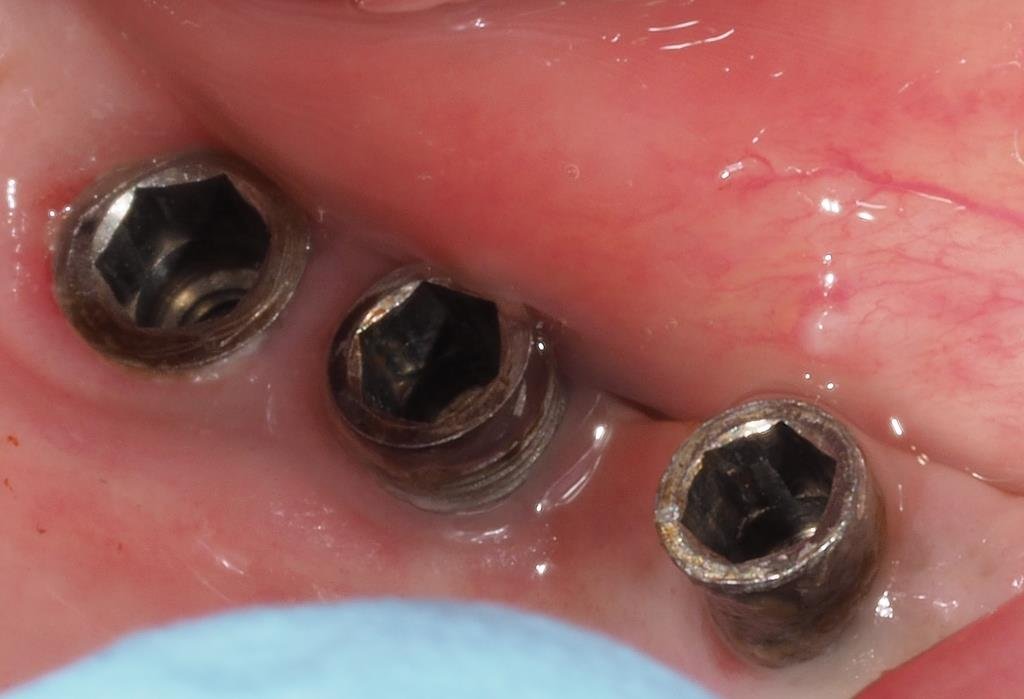

Buenas tardes Me llega este paciente de idental y soy incapaz de reconocer los implantes agradecería ayuda para identificarlos Muchísimas gracias

El paciente presenta movilidad en la corona del 25, y necesitamos saber de qué tipo de implante se trata para poder solicitar el instrumental necesario, ya que no quiere volver [...]

Hola , no sabemos que implante son el de 24 y 25 , si me podeis ayudar gracias.